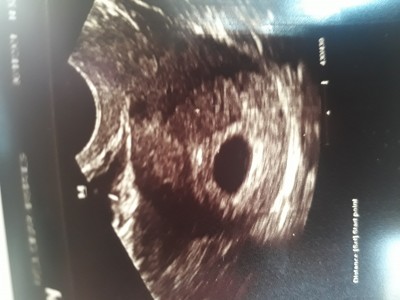

3 Kasım 2021 Hamilelik Dönemi Genel kategorisinde (8 puan) sordu

7+ 4 kese gozukmedi ayni durum yasayan varmi

Gebelik haftası 7+4